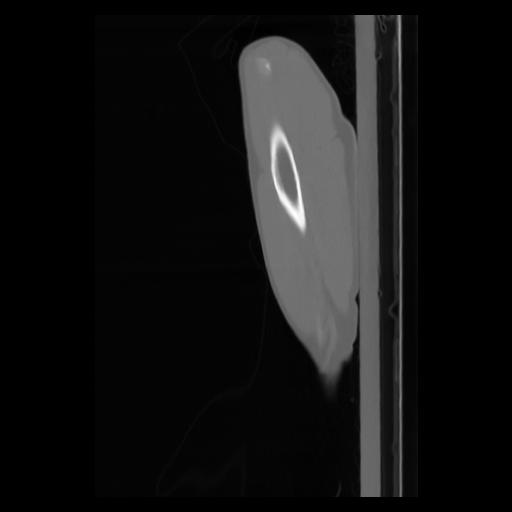

30 CUERPO,CE,Sagittal,3.000,CUERPO,Sagittal,